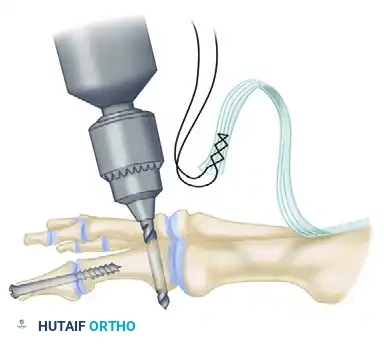

Step 4: IP Joint Fixation (Shives and Johnson Technique)

Rigid internal fixation is paramount for a successful arthrodesis. The use of a 4.0-mm cancellous lag screw, as advocated by Shives and Johnson, provides excellent compression and rotational stability.

- Retrograde Drilling: Drill a 2.0-mm diameter hole longitudinally in a retrograde manner starting at the center of the denuded articular surface of the distal phalanx.

- The drill bit should exit the skin at a point exactly 5 mm plantar to the tip of the nail in the midline of the toe.

- Antegrade Drilling: Appose the denuded articular surfaces of the proximal and distal phalanges in neutral alignment. Insert the drill bit distally at the tip of the toe (through the previously created exit hole) and advance it proximally.

- Follow the previously placed retrograde hole, cross the IP joint, and drill into the base of the proximal phalanx, advancing down the center of its medullary canal.

- Overdrilling and Tapping: To achieve a true lag effect, overdrill the distal phalanx (the near cortex) with a 2.7-mm drill bit to create a gliding hole. Tap the entire drill path with a 3.5-mm tap to prepare for the cancellous screw.

- Screw Insertion: Following the drill path in a proximal direction, insert a 4.0-mm partially threaded cancellous bone screw.

- As the screw head engages the distal phalanx, the lag effect will produce robust compression across the arthrodesis site, ensuring firm fixation.

- Prepare a drill hole through the base of the proximal phalanx from lateral to medial. Pass the EHL tendon through this osseous tunnel.

- Apply tension to the EHL tendon while holding the MTP joint in approximately 10 to 15 degrees of extension and neutral coronal alignment (correcting the varus).

- Suture the tendon back onto itself using non-absorbable braided suture (e.g., #2-0 FiberWire or Ethibond) to secure the transfer under appropriate physiological tension.